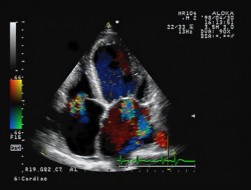

外来でできる検査(心電図,心エコー図,運動負荷心電図,ABI,冠動脈CT等)

| ▲心エコー検査機器 | ▲心臓の断面がよくわかります |